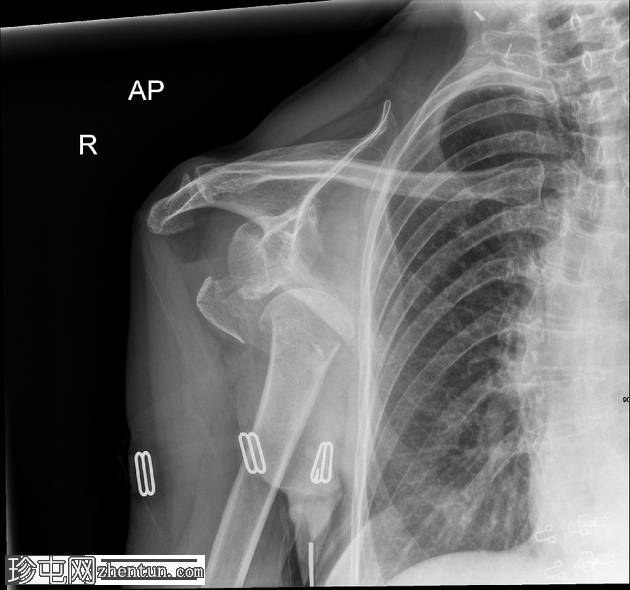

2.png

斜位

右肱骨近端粉碎性骨折,严重移位,累及肱骨颈和肱骨大结节,伴肱骨近端相对于肩胛盂的前下脱位和肩关节脂肪血肿。肩锁关节完整;另可见胸椎侧弯、右侧颈部手术夹以及覆盖上臂和腋窝的衣物痕迹。

该X线片显示右肩高能量损伤,表现为肱骨近端粉碎性骨折,严重移位,累及肱骨颈和肱骨大结节。伴随的前下肩关节脱位反映了稳定软组织结构的破坏,这是此类骨折脱位模式的常见特征。脂肪血肿的存在表明骨折已延伸至关节内,骨髓脂肪渗入关节腔;这是评估损伤严重程度的重要影像学线索。